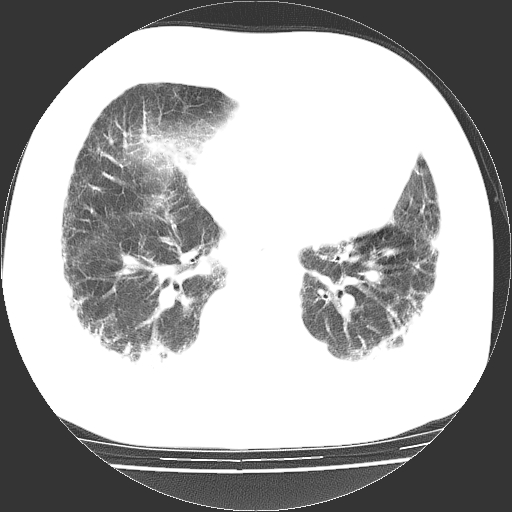

男,68岁,咳嗽、胸闷、发烧三天,查体:双肺散在湿罗音。

首先考虑特发型肺间质纤维化;两侧少量胸腔积液。

依据:1、两肺广泛条索状、网格状、蜂窝状改变。

双肺多发条索状、网格状及小灶状密度增高影。考虑慢支合并感染.间质纤维化,双侧少量胸腔积液

两肺广泛条索状、网格状、蜂窝状改变。肺间质纤维化,肺心病,双侧胸腔积液